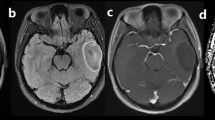

Tables 2 and 3 give the (semi-)quantitative measurements of aMRI for LGOs and HGOs. Relevant MRI images are depicted in Figs. 1 and 2. nADC values from DWI were significantly higher in LGOs than in HGOs (P < 0.001). ITSS levels of HGOs were substantially greater than that of LGOs with seven (46.7%) HGOs which exerted an agglomerated or nodular appearance of ITSSs (P = 0.006). Both nCBV and nCBF values in HGOs were significantly higher than the values of LGOs (P < 0.001 and P = 0.005).

A 55-year-old man with molecularly defined LGO. On axial T2WI (a), the lesion shows homogeneous signal. Axial CE-T1WI (b) demonstrates absence of contrast enhancement. Corresponding ADC maps (c) show an increased ADC value (nADC = 1.52). rCBV maps (d) show significantly reduced perfusion with the calculated nCBV of 1.12. SWI (e) presents nearly no evidence of ITSS. H&E staining (×100) photomicrograph (f) reveals a low cell density